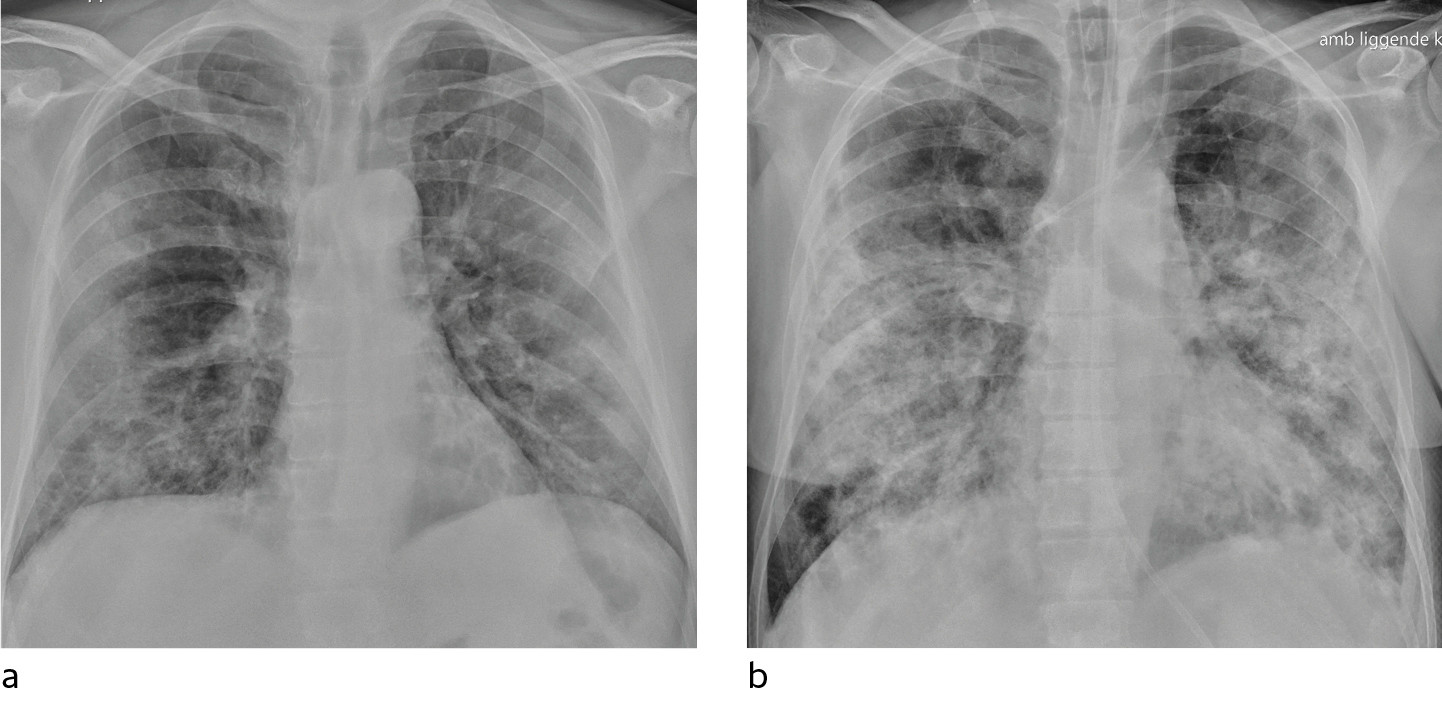

In a dataset from Hong Kong, 69 % had findings on chest X-rays prior to treatment (baseline), but 9 % had findings on chest X-ray prior to positive PCR (14). Sensitivity for chest X-ray was 69 % and for PCR 91 %. The most common X-ray findings were bilateral consolidation and ground-glass opacities with peripheral and caudal distribution. The findings were most pronounced 10–12 days after the onset of symptoms. Figures 1 and 2 show typical chest X-ray patterns in patients with COVID-19.

Typical CT findings vary with symptom duration and can be divided into three stages: an early phase, an intermediate phase that extends from 3–5 days after symptom onset, and a late phase.

There are not always CT findings the first few days after symptom onset. In a material with symptomatic, but unspecified patients, 56 % had normal CT findings within two days of symptom onset (12), declining to 9 % 3–5 days after symptom onset and 4 % 6–12 days after symptom onset. The frequency of findings varies with the severity of the disease. Initial diagnostic imaging yielded normal findings for 18 % in a cohort of patients who were not severely ill, but in only 3 % of patients who were (15). Typical CT findings are multiple, bilateral ground-glass opacities with peripheral distribution, most frequently located in the lower lobes. In the intermediate phase there are increasing amounts of consolidation and affection of several lobes, and increased septation with crazy paving as sign of interstitial affection. In the late phase there is increasing total extension, but ground-glass opacities and consolidation are still the dominant findings (12, 16). Figures 4, 5 and 6 show typical CT findings in different phases of COVID-19.